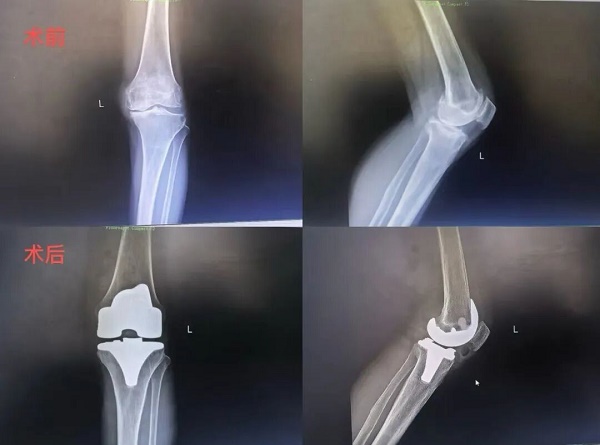

入院后,骨伤科团队为患者进行了详细检查。膝关节CT及X线片显示,患者膝关节关节间隙明显狭窄、软骨磨损严重、骨质增生形成,符合重度膝关节骨性关节炎的诊断标准,膝关节表面置换手术指征明确。

考虑到患者年龄较大、病程较长,骨伤科团队联合麻醉科、心血管内科、康复科等进行多学科会诊,全面评估手术风险,制定了个性化手术方案及应急预案。经过充分术前准备,团队为患者成功实施膝关节表面置换手术,术中精准切除病变软骨及骨赘,安装人工膝关节假体,重建膝关节功能。